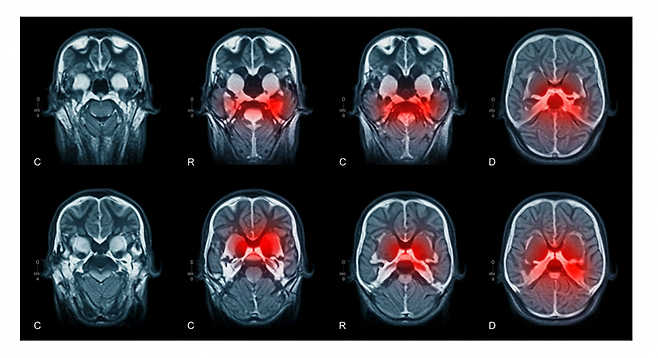

뇌경색의 가장 큰 특징은 갑작스럽게 나타난다는 것입니다. 다음 증상들이 갑자기 발생하면 즉시 병원을 찾아야 합니다.

- 얼굴, 팔, 다리에 갑자기 힘이 빠짐

- 말이 어눌해지거나 이해력이 떨어짐

- 시야가 흐려지거나 복시 현상

- 경험해본 적 없는 극심한 두통

- 걸음걸이가 불안정하고 어지러움

미니 뇌졸중도 방심은 금물